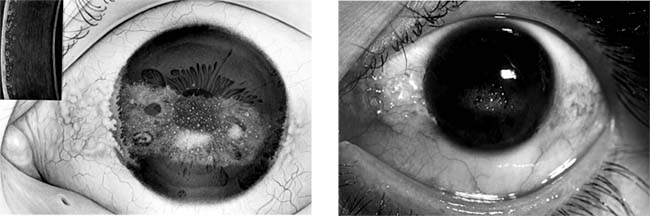

Climatic Droplet Keratopathy (Labrador Keratopathy, Spheroid Degeneration of the Cornea) (new window  Figure 6-13)

Figure 6-13

Figure 6-13: Two photos showing climatic droplet (Labrador) keratodystrophy. Inset at left shows slitlamp view. (Photo at left courtesy of A Ahmad.)